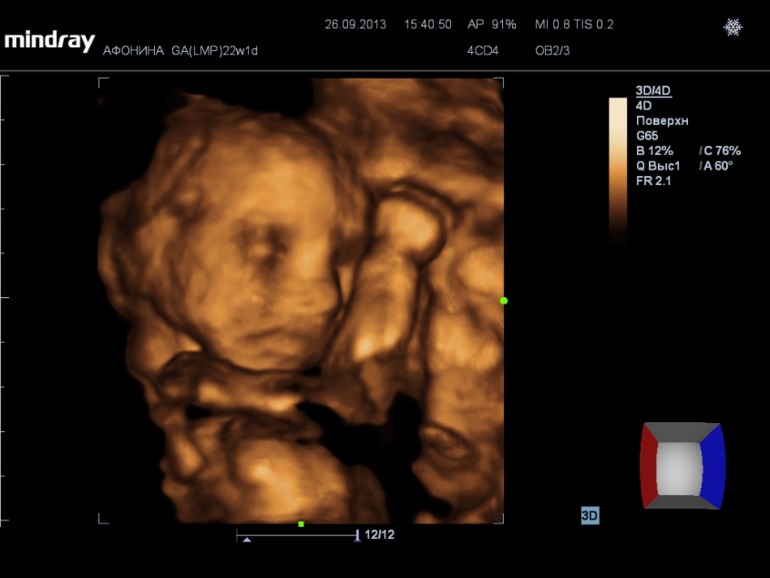

На 3d нам сказали что ребеночек ну очень щекастый, нос картошкой))) Наделали кучу фото и видео (запись на диск 300р), насмотрелись вдоволь. А в самом конце нам сказали пол.....

у нас будет девочка!!!!!!!!!!!!!!!!!!!!!

А вот и фото нашей принцессы))) (под кат)